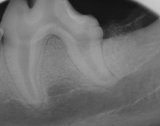

Xray of extracted molars

Post operative xray of extracted second and third molars.